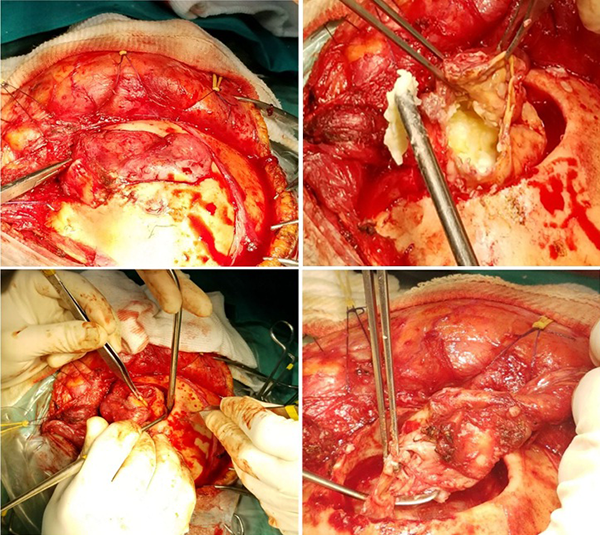

Debido a los hallazgos imagenológicos y clínicos, se decidió realizar su exéresis quirúrgica (Figuras 3 y 4).

Figura 3. Imágenes intraoperatorias. Tiempo extradural.

Figura 4. Imágenes intraoperatorias. Tiempo extra e intradural. Flecha amarilla: defecto dural a través del cual se comunica el espacio extra y subdural.

Se planificó un abordaje hemicoronal izquierdo pasante de línea media. El colgajo cutáneo se disecó en dos planos. Se constató el compromiso del plano subgaleal y de la fascia superficial del músculo temporal por parte de la lesión. La misma se disecó de forma circunferencial siguiendo su trayecto hacia su origen en la calota craneana y se obtuvo muestra de contenido del saco, el cual se describe como “blanco perlado”, de aspecto caseiforme, evacuándolo mediante aspiración en su totalidad. La cápsula tumoral detergida se disecó del borde óseo y la duramadre hasta rodear en 360° el sitio de perforación de la misma. Se realizó ligadura y exéresis del componente extradural del saco. Luego, se efectuó un fresado circunferencial del borde óseo, hasta observarlo sano.

El tiempo intradural se inició con la apertura dural centrada en el defecto de perforación a través de la cual se desprendió material caseoso de similares características al evacuado previamente. Se realizó lavado y aspiración de la cavidad intracerebral. Se visualizó una pseudocápsula friable sin plano de disección, lo que dificultó su exéresis completa a pesar del intento. Para finalizar, se llevó a cabo la exéresis de duramadre adelgazada e infiltrada, con posterior plástica dural con parche autólogo y se realizó un cierre cutáneo por planos.